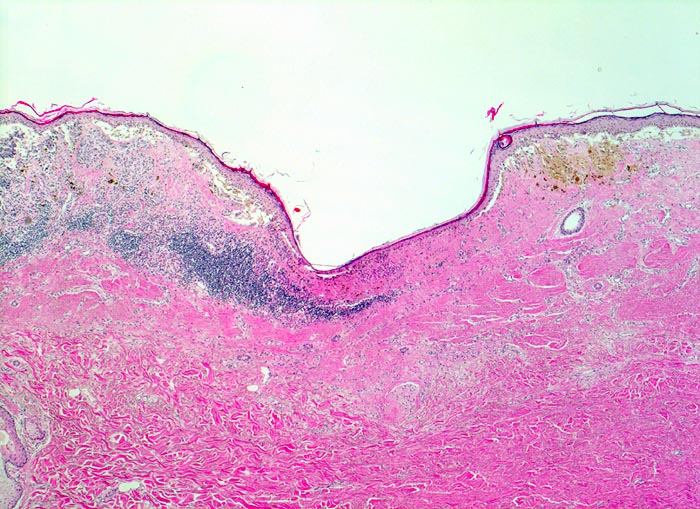

Malignes Melanom

Asymmetrischer, in der oberen Dermis gelegener, teils pigmentierter Tumor mit begleitendem perifokalem Entzündungsinfiltrat. Fokal fehlen Tumorzellen (Regression). Anstelle der Tumorzellen narbenartige Fibrose und Entzündungszellen.

Stellenweise erhabene, unregelmässig begrenzte und inhomogen gefärbte braun-schwarze Hautläsion.

Rasch gewachsene Hautläsion am Unterschenkel.

Der oberflächliche Anteil maligner Melanome zeigt oft Zeichen der Regression. Die Zerstörung der Tumorzellen durch das körpereigene Immunsystem hinterlässt in der papillären Dermis eine narbenartige Fibrosezone, Gefässneubildungen und Melanophagen. Bei vollständiger Regression eines malignen Melanoms kann es vorkommen, dass trotz metastasierendem Tumorleiden kein Primärtumor gefunden wird.